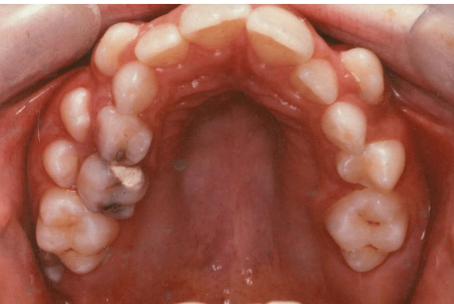

which caries risk category

why (3)

high

existing restorations in 85, 84, 74

buccal swelling adjacent to 85

new carious lesion in 75

which 2 teeth have been temporised

85

84

which tooth is erupting distal to the last tooth on patients RHS

46

at what age do 6s usually erupt

6 years

what preventative tx would you provide for 46 when erupted

fissure sealant

5 possible fluoride containing preparations and doses, which would be suitable for this pt who lives in an area with less than 0.3ppm fluoride in drinking water